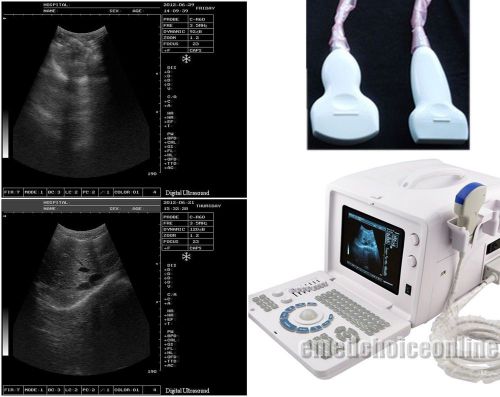

Brand | Ultrasound 9000E2 |

| MPN | Full Digital Ultrasound | ||

| Model | HIGH RESOLUTION | ||

2 probes+3D Digital Ultrasound Scanner+3.5MHz Convex 7.5MHz Linear probe CE DFA

Full Digital Portable laptop Ultrasound Scanner system CONVEX+LINEAR TWO PROBE